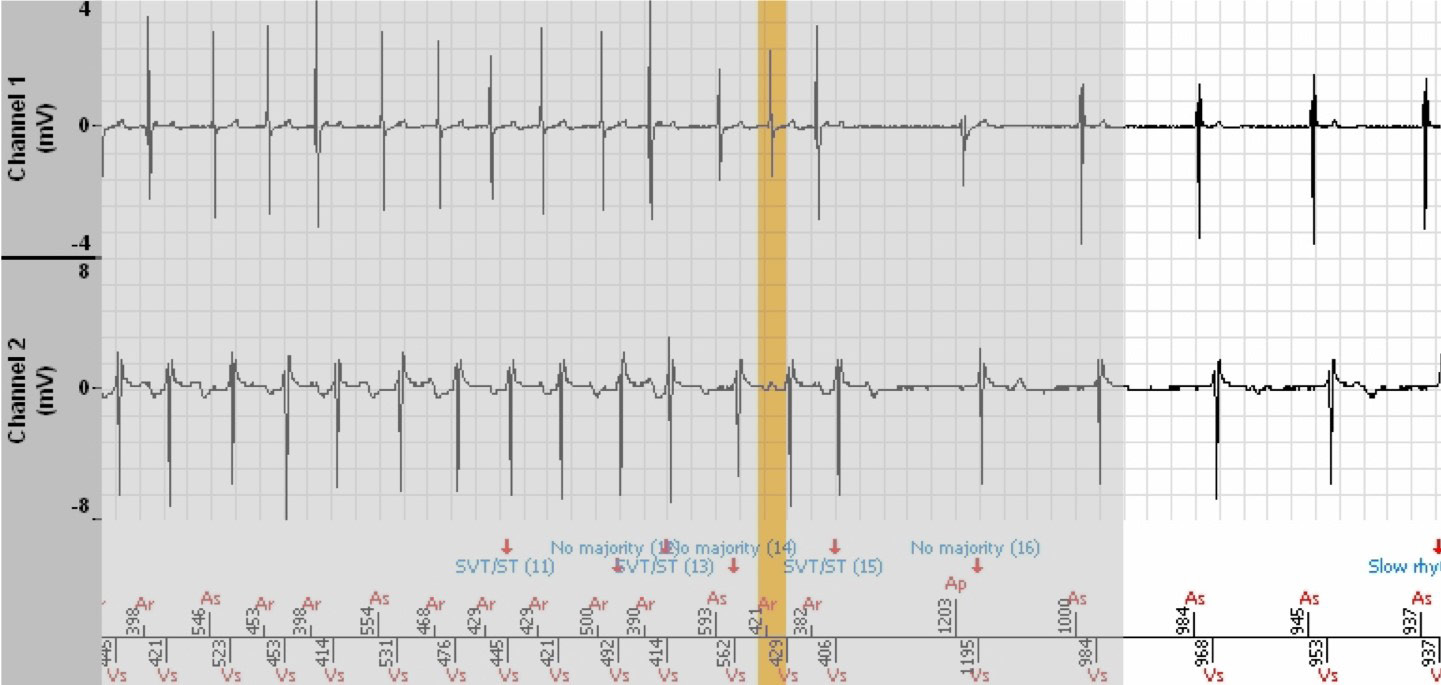

The shaded areas are the portions of the EGM that are the repetitions of the end of the previous image.

- The tachogram reveals both atrial and ventricular premature contractions during conducted sinus rhythm.

- The tachycardia is preceded by a ventricular triplet with probable retrograde conduction, followed by an immediate destabilisation of the atrial rhythm which initiates an unstable atrial tachycardia and reflected in the ventricle, leading to the

diagnosis is SVT. Each variation of the P’P’ interval induces the same variation of the corresponding RR interval. The tachycardia is well controlled by the atrium.

- The diagnosis is No majority when the rhythm enters or returns in the Slow zone (non Tachy) for at least 3 out of 8 cycles (but less than 6), then again becomes unstable with a diagnosis of SVT until termination of the episode.

- No therapy was induced.

- The rhythm is viewed as stable, 1:1, with A acceleration, hence the diagnosis of SVT.

- Of note: the atrial markers are either As or Ar during the entire episode. This signifies that the defibrillator is constantly suspicious of atrial arrhythmia identified by the Fallback Mode Switch algorithm that functions in parallel. The As markers appear when

the Ar-As interval is greater than 500 ms. This is not specific to the defibrillator, but to the Fallback Mode Switch algorithm of all platforms of the brand, both pacemakers and defibrillators.